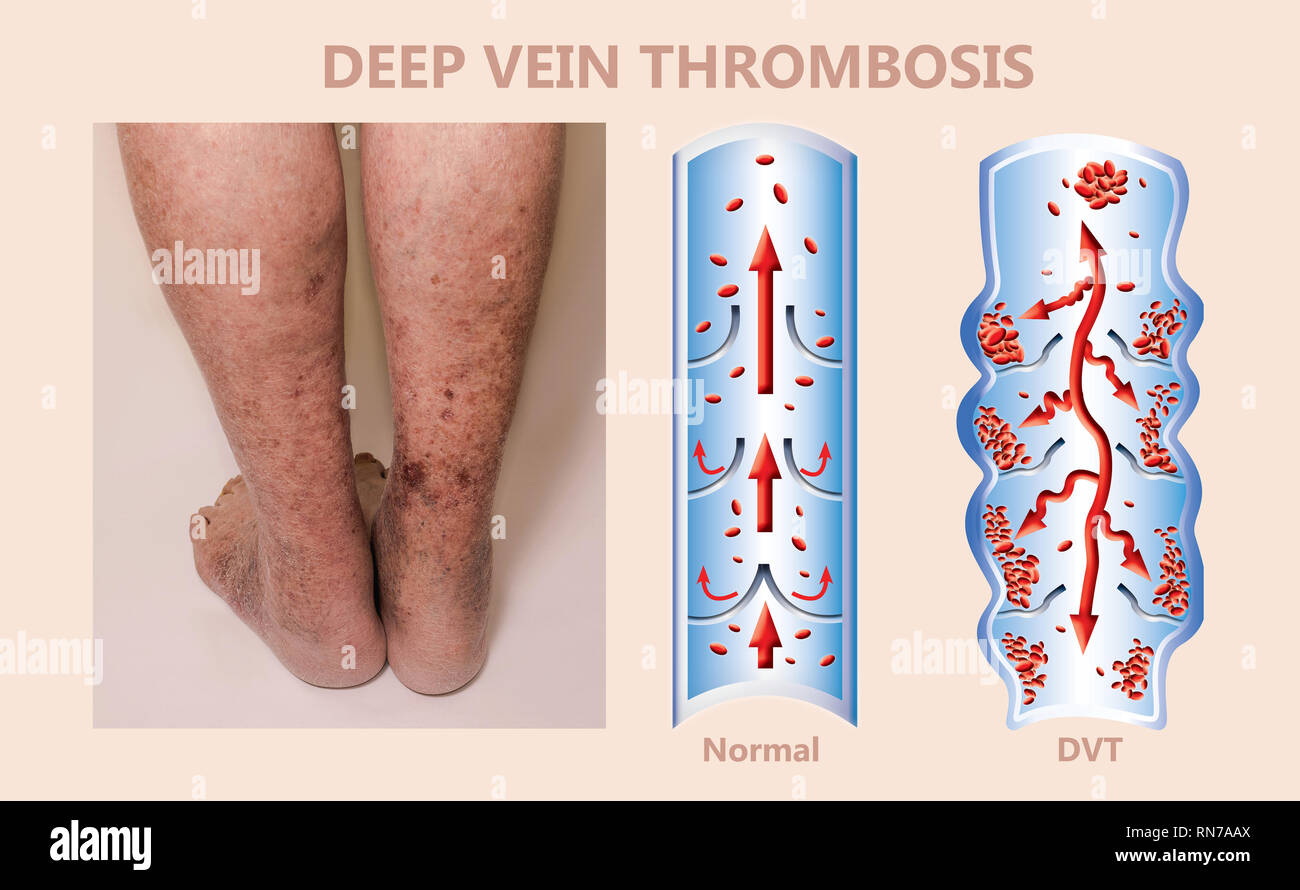

RM2H1FTKC–Syndrome mécanisme, thrombose veineuse profonde ou embolie pulmonaire, thrombose ou PE, thrombose coronaire, illustration du schéma de jambes mâle

RFRN7ABR–Syndrome mécanisme, thrombose veineuse profonde ou d'une thrombose veineuse profonde, embolie pulmonaire, thrombose coronaire, schéma

RFRN7AAX–Syndrome mécanisme, thrombose veineuse profonde ou d'une thrombose veineuse profonde, embolie pulmonaire, thrombose coronaire, schéma